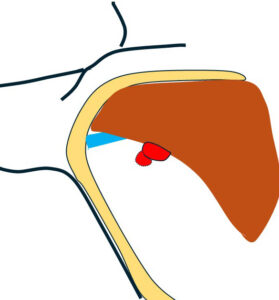

リンパ節の形態を失って「節外浸潤」している

レベル2リンパ節 これが一番大きい 2㎝

形はリンパ節の形をしており「節外」では(画像上)なさそう。

大きなレベルⅡは、レベルⅢに近い部位までせり出し、その奥(図中央)にはレベルⅢが

確認できる。

←外側 (皮膚側) 内側(奥)→